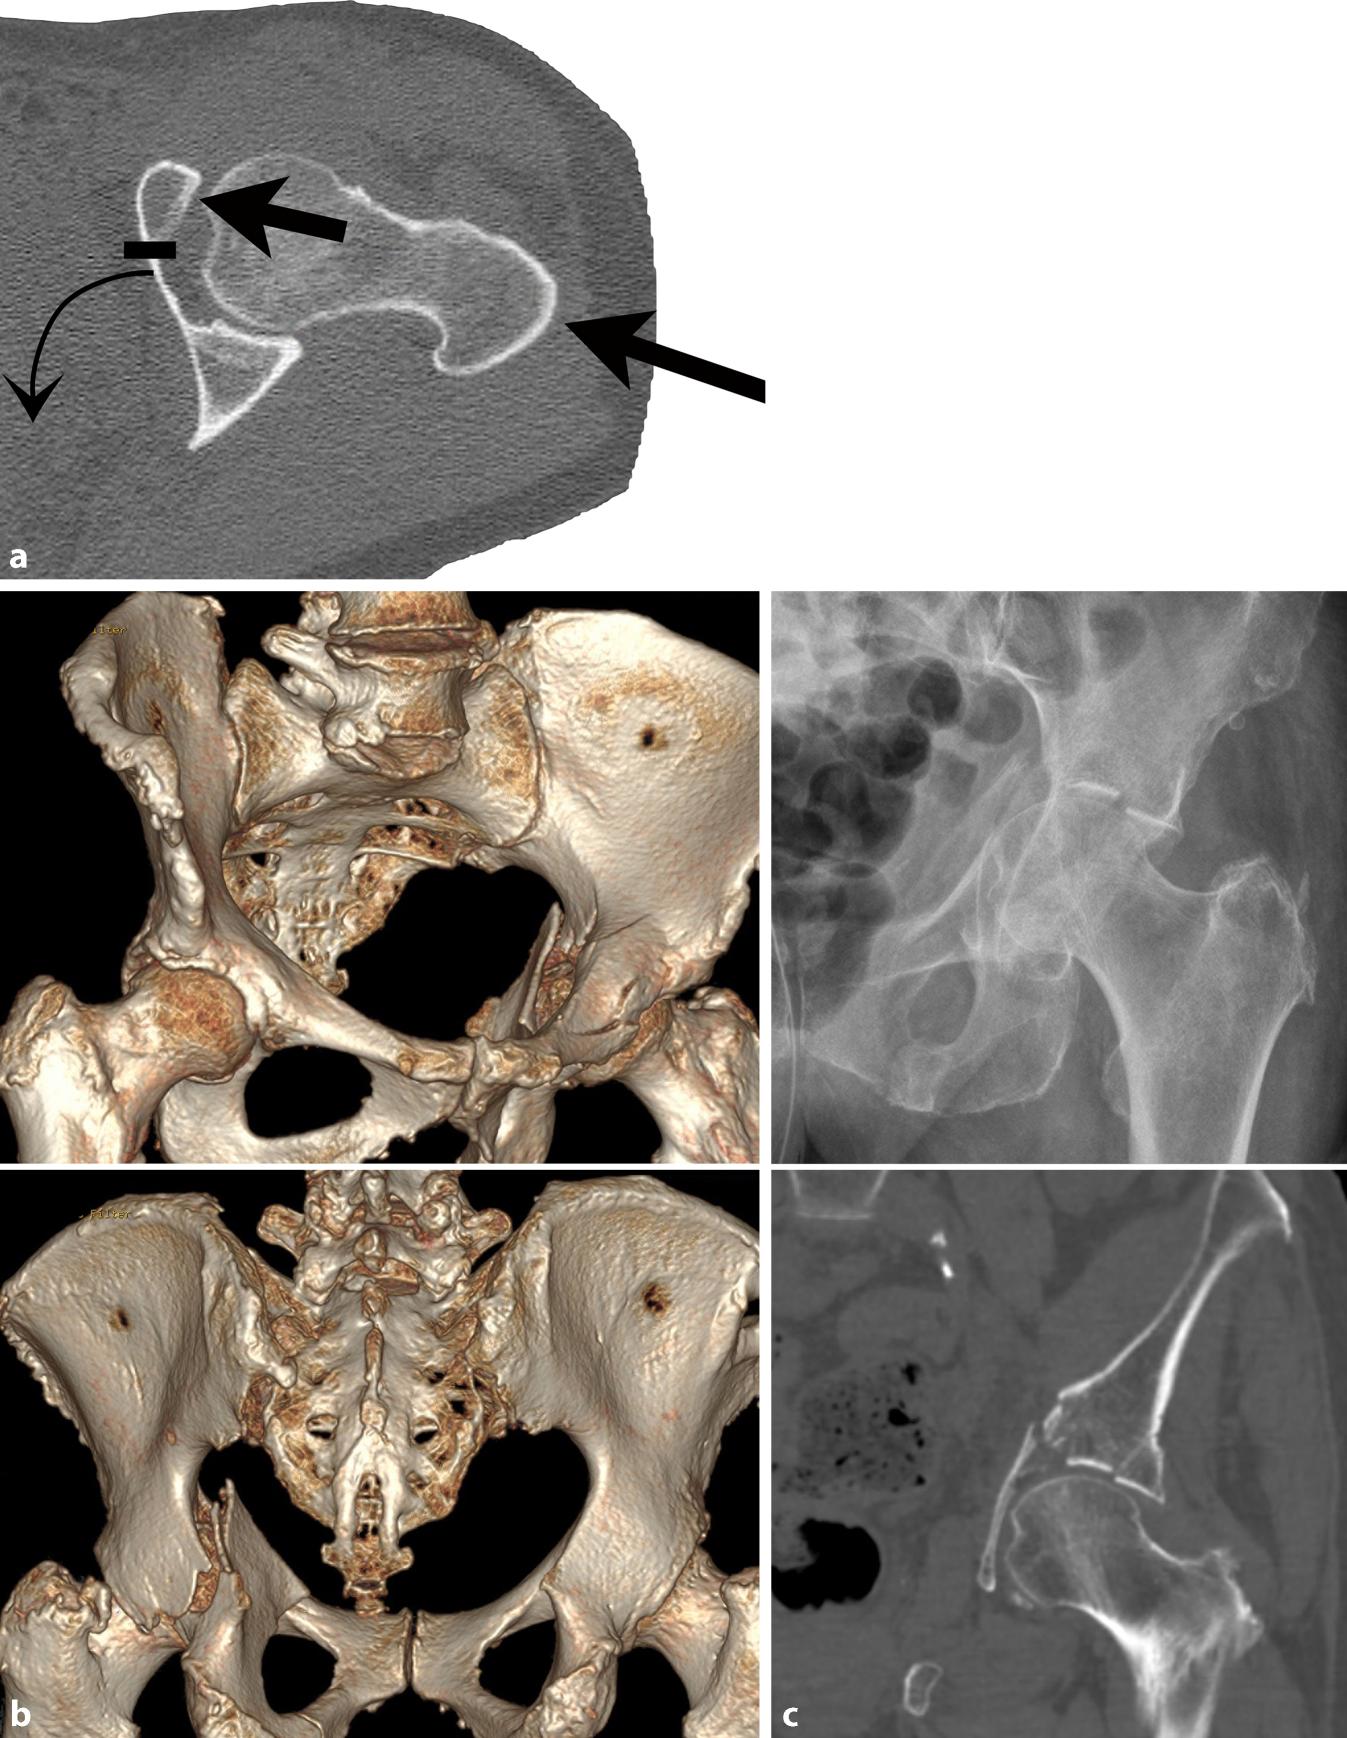

Fig. 6

a Posterior column screw—fracture type. A 67-year-old man who sustained a bicycle accident with a direct impact on the left hip. The CT scan shows an anterior column with posterior hemitransverse fractures (ACPHF) with a multifragmentary fracture of the anterior column. The quadrilateral plate is internally rotated and in osseous continuity with the posterior column. The posterior hemitransverse fracture is simple as shown in b. b Preoperative planning—posterior column screw trajectory. The medial angle of the posterior column screw trajectory is 16° to the sagittal plane (left) and the posterior angle is 24° to the coronal plane (right). The maximum screw length is 123 mm. c Preoperative planning—estimation of the starting point and the endpoint. The starting point and the end point are determined using the LiveSync feature as described in Fig. 3. d Intraoperative application—fluoroscopic control in anterior–posterior (ap) view. The anterior column fracture was reduced via a modified Stoppa approach and stabilized with two 3.5 pelvic reconstruction plates. The posterior hemitransverse fracture was indirectly reduced by reducing the quadrilateral plate. The starting point for the posterior column screw was approached via a small incision at the iliac crest and submuscular preparation under fluoroscopic control in the ap view. The guide wire was advanced according to preoperative planning (b). It is advisable to switch to the lateral–oblique view when approaching the hip joint. After predrilling, a cannulated 6.5 mm screw with a 32 mm thread and a length of 115 mm was inserted. The screw length must not be longer than the maximum length determined in preoperative planning, but may be shorter provided that the screw thread completely passes the fracture line. The fluoroscopic control shows a screw trajectory as preoperatively planned (c). e Intraoperative application—fluoroscopic control in lateral–oblique view. The left hip joint is located next to the radiation source which results in a “larger” left hip joint. Additionally, the radiation source is tilted 15° upwards resulting in a more posterior projection of the left hip. The lateral–oblique view shows that the screw does not penetrate the hip joint and does not perforate the cortical bone of the posterior column and the sciatic tuber. f Postoperative CT control. The correct screw trajectory is confirmed in the postoperative CT scan. The posterior hemitransverse fracture is anatomically reduced